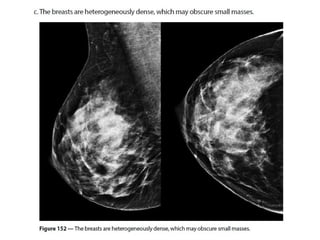

• 1.

Breast imaging basedon ACR2013 MD .Dr.k.sharifi.radiologist